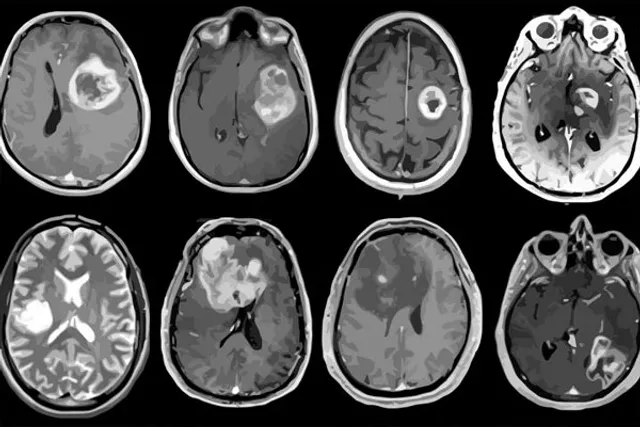

Madrid:  Researchers have obtained a highly accurate recreation of human glioblastoma's features using a novel 3D microscopy analysis.

This new analysis of 3D images and quantitative data "will help to appreciate from within how the tumor is built in its full dimensionality, and to identify where different cell types are located," explained researcher George Paul Cribaro from the Universitat AutAnoma de Barcelona.

"It provides more complete information than the usual 2D analyses performed for neuropathological diagnosis," Cribaro added.

With this new approach, the research team showed the alterations in tumour blood vessels, and that these vascular wall abnormalities do not hinder the entrance of lymphocytes T (potential defense against tumoral cells), which is relevant for the design and use of immunotherapies targeting malignant cells.

Moreover, the images allow the tumour to be differentiated into two areas, the tumor tissue properly speaking, and the stroma, which gives support to the tumor, in which there are different immunological microenvironments, the team said.